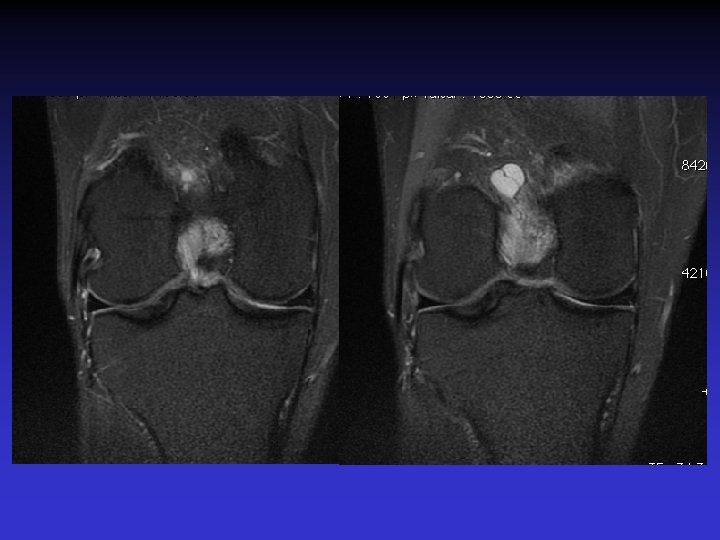

• • • Pas d’épanchement Pas de lésion méniscale Pas de lésion cartilagineuse Pas de lésion osseuse Anomalies du LCA • Épaissi • Hyper signal T 1 et T 2 • Orientation des fibres conservée • Kyste

ASPECT IRM • • Hyposignal TI Hypersignal T 2 Pas de prise du contraste après Gado IV Continuité conservée du LCA+++ avec dilacération des fibres • Aspect en « tige de céleri »

GEODES SYNOVIALES • En regard des zones d’insertion fémorale et / ou tibiale • Hypo TI Hyper T 2 • Rehaussement possible après Gado IV